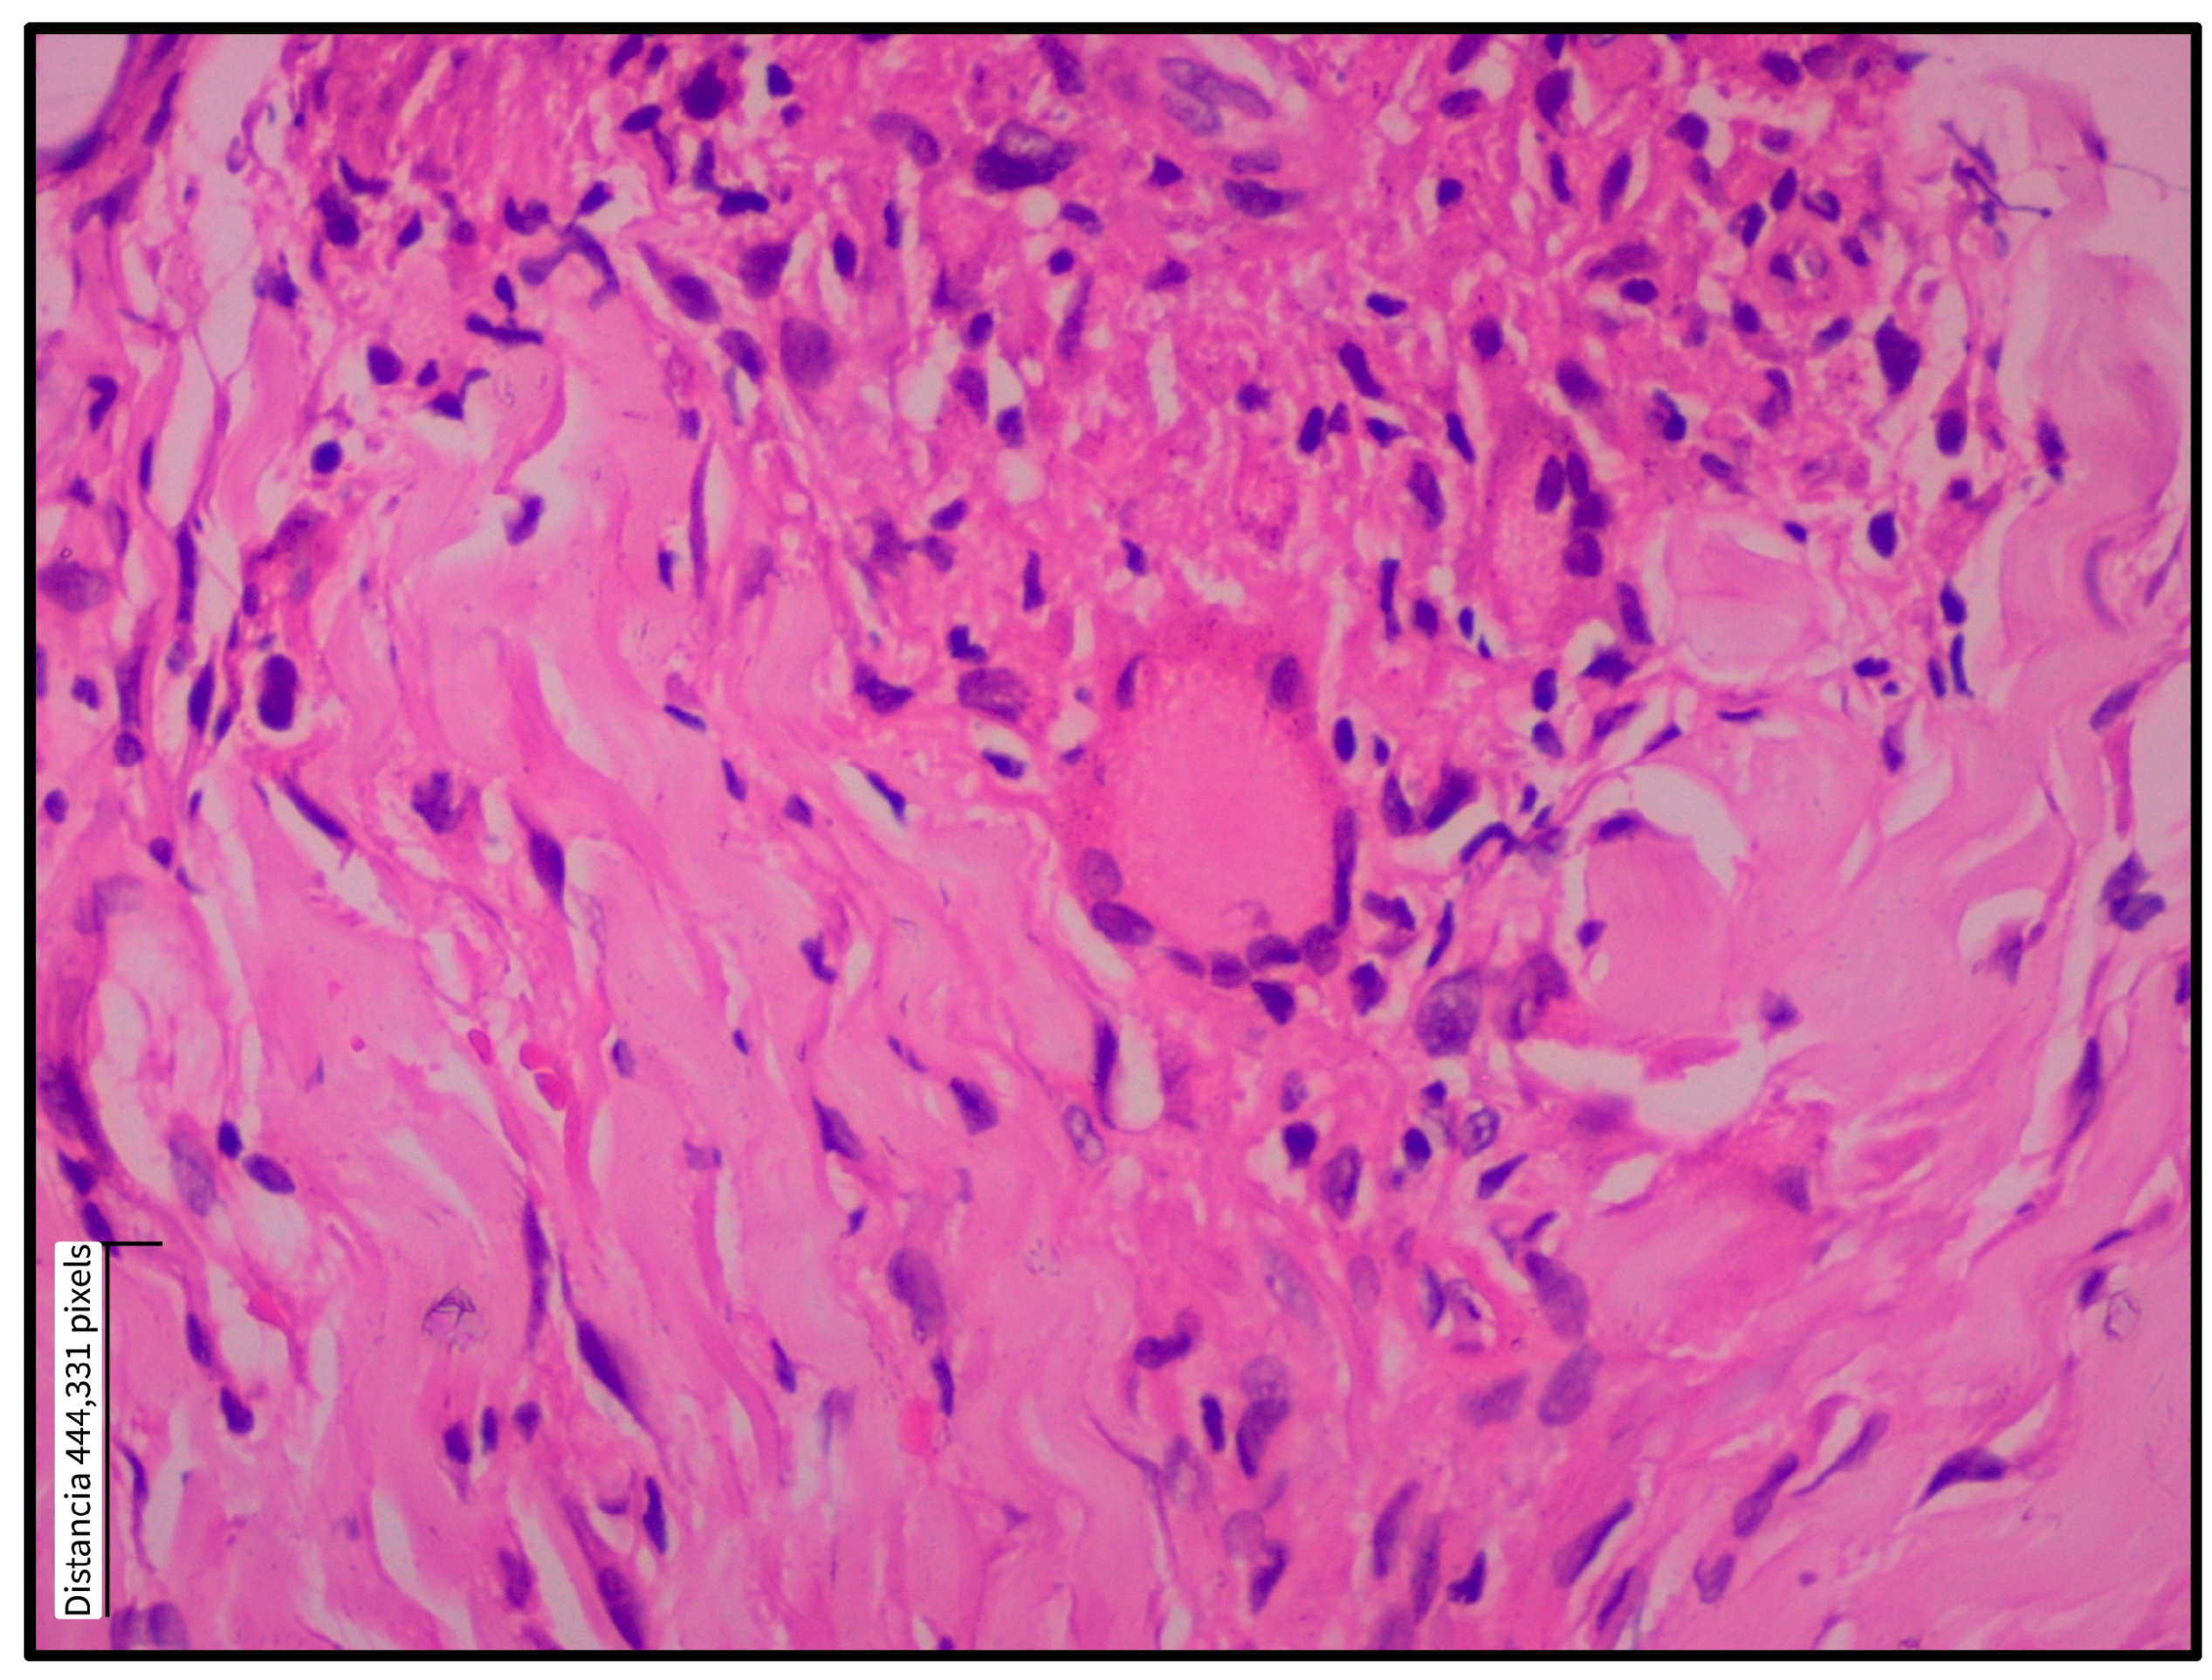

3.1. Histopathological Findings

| Tissue Level | Histological Feature | n = 16 (%) | |

|---|---|---|---|

| Epidermis | Ulceration | 14 (87.5) | |

| Acanthosis | 15 (93.8) | ||

| Pseudoepitheliomatous hyperplasia | 14 (87.5) | ||

| Spongiosis | 13 (81.3) | ||

| Parakeratosis | 13 (81.3) | ||

| Transepidermal migration | 8 (50.0) | ||

| Dermis | Inflammation | 15 (93.8) | |

| Granulomatous pattern | 10 (62.5) | ||

| Fibrosis | 10 (62.5) | ||

| Vascular proliferation | 13 (81.3) | ||

| Vascular type | Telangiectasias | 6 (37.5) | |

| Prominent endothelium | 8 (50.0) | ||

| Inflammatory cell type | Abundant | Scant | |

| Plasma cells | 11 (68.8) | 5 (31.3) | |

| Lymphocytes | 13 (81.3) | 3 (18.8) | |

| Histiocytes | 6 (37.5) | 10 (62.5) | |

| Infiltrate classification | Mixed-type granuloma (100) | ||

| Infiltrate distribution | Perivascular | 0 (0) | |

| Interstitial | 0 (0) | ||

| Diffuse | 14 (87.5) | ||

| Nodular | 2 (12.5) | ||

| Granulomas | Tuberculoid | 3 (18.8) | |

| Epithelioid | 9 (56.3) | ||

| Sarcoid | 0 (0) | ||

| Giant cells | Multinucleated | 3 (18.8) | |

| Langhans-type multinucleated | 6 (37.5) | ||